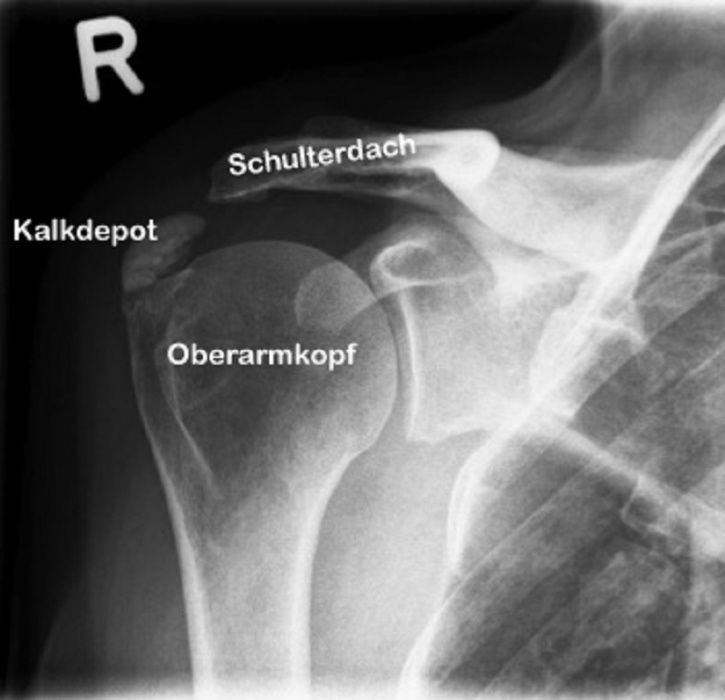

Unter einer Kalkschulter versteht man die ‘Verkalkung’ im Schulterbereich. Diese Verkalkung ist meist verschleißbedingt und nicht bröckelig-steinig, wie häufig falsch angenommen wird; sie ist eher pastös wie Zahnpasta. Die Kalkschulter kommt bei 2,7-20 % der Allgemeinbevölkerung vor, zumeist sind Personen zwischen dem 30. und 60. Lebensjahr davon betroffen. Bei 1/3 der Betroffenen bereitet die Kalkschulter jedoch keine wesentlichen Beschwerden und gilt somit als ‘Zufallsbefund’ im Röntgenbild. Die Ursache der Kalkschulter ist unklar; diskutiert wird hier neben einer vererblichen Komponente auch das Enge-Syndrom im Schulterdachbereich (das sogenannt ‘Impingement-Syndrom’).

Beginnen die Beschwerden ohne erkennbare äußere Ursachen (Unfall etc.), sollte eine Röntgenaufnahme erfolgen, da eine mögliche Verkalkungsstruktur hierbei deutlich erkennbar gemacht wird. Um dann eine weitere wesentliche Veränderung wie einen Riss oder eine Destruktion der Rotatorenmanschette auszuschließen, sollte ein ergänzendes MRT der Schulter durchgeführt werden.